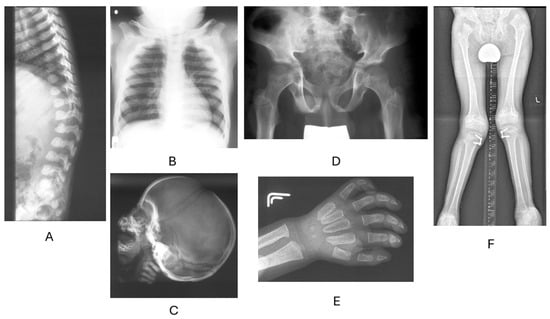

3.3. Skeletal Features

- Borgo, A.; Cossio, A.; Gallone, D.; Vittoria, F.; Carbone, M. Orthopaedic challenges for mucopolysaccharidoses. Ital. J. Pediatr. 2018, 44 (Suppl. S2), 123. [Google Scholar] [CrossRef]